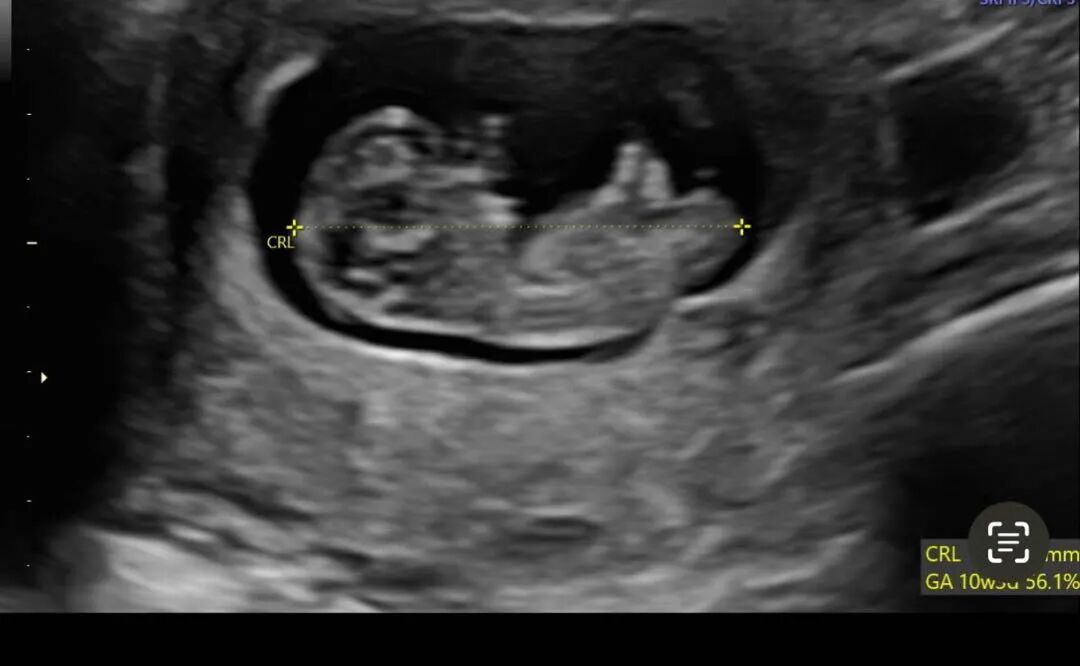

移植进行中...

移植进行中...在生育专家的精湛技术指导下,一枚健康的胚胎已经顺利完成移植!我们的准父母是一对来自日本的夫妇,现居西雅图,之前找我们成功匹配捐luan女生制作了6个胚胎。相信在经验丰富的爱妈H的悉心照料下,一起期待不久后的好消息吧!

爱妈T的孕期旅程再次启程!来自加州的她,伴随着另一半的支持,再次踏入诊所进行孕期体检。上次她帮助一位单身准爸爸迎来了他们的混血小天使。六个月后,爱妈T再次匹配,这次她将帮助一对夫妇实现成为父母的梦想。

最近我们见证了很多位爱妈的移植日,且都迎来非常顺利的着床结果,又一天新的移植日来啦!爱吗J来自明尼苏达州,她已经是三个孩子的母亲,爱妈J拥有一个幸福的家庭和丰富的育儿经验。她满怀信心地飞到纽约接受胚胎移植,在我们诊所专家的精确操作下,移植过程非常顺利。